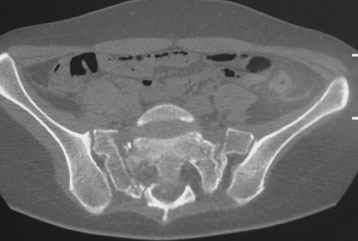

Травма 21.августа 2005г. На девочку в лесу упала береза. Доставлена в ближайшую ЦРБ. При поступлении установлен диагноз: Травматический шок 2-3 ст. Тупая травма живота. Забрюшинная гематома. Перелом костей таза с нарушением целостности тазового кольца. Перелом лонной и седалищной костей справа. Перелом поперечных отростков L3 - L5. Разрыв КПС справа. При поступлении выполнена диагностическая лапароскопия — выявлена обширная забрюшинная гематома. Было наложено скелетное вытяжение за бугристости обеих б/берцовых костей, больная уложена в гамак. Через неделю скелетное вытяжение демонтировано, гамак снят. Девочка уложена в положение «лягушки». Контрольные рентгенограммы через 4 недели после травмы. Заподозрен перелом дужки L5. Больная 26 сентября 2005 г. переведена в областную больницу в отделение детской ортопедии. При поступлении в локальном статусе: пальпация и перкуссия остистых и поперечных отростков L4-5 болезненная. Пальпация костей таза б/болезненная. С-м натяжения слабо положителен. Осевая нагрузка положительная. Движения в т/б суставах ограничены, болезненны. C-м прилипшей пятки отрицательный. C-м Ларрея и Варнейля отрицательный. Периферическая гемодинамика не нарушена.Неврологический статус: вторичная двусторонняя радикулопатия L5-S1. 29 сентября произведена компьютерная томография позвоночника и таза.

Судя по томограммам, радикулопатия может быть из-за компресии "конского хвоста" смещенным крестцовым позвонком, это хорошо видно на втором слева снимке. Если этот сегмент будет нестабилен и будет сохраняться неврологическая симптоматика, придется оперировать. Если неврологическая симптоматика уйдет и перелом стабилизируется, то можно обойтись без операции.